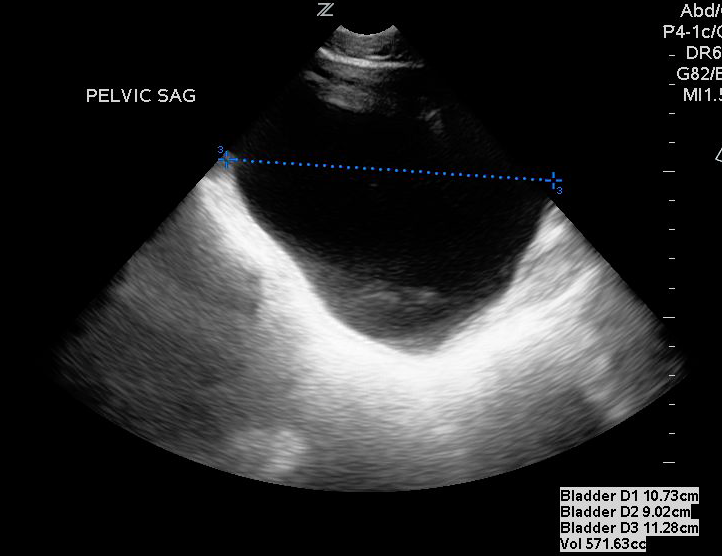

- For measuring bladder volume, use the US volume measurement feature or the formula 0.52 × Depth × Width × Height.

- In the transverse view, find the largest bladder size and measure both the vertical and horizontal length of the bladder image from inner wall to inner wall. This corresponds to the bladder depth and width, respectively.

- In the sagittal plane, measure the maximum horizontal length of the bladder image from inner wall to inner wall. This corresponds to the bladder height.

- Figures 3 and 4. Measurement of bladder volume in the transverse (Figure 3) and sagittal (Figure 4) views